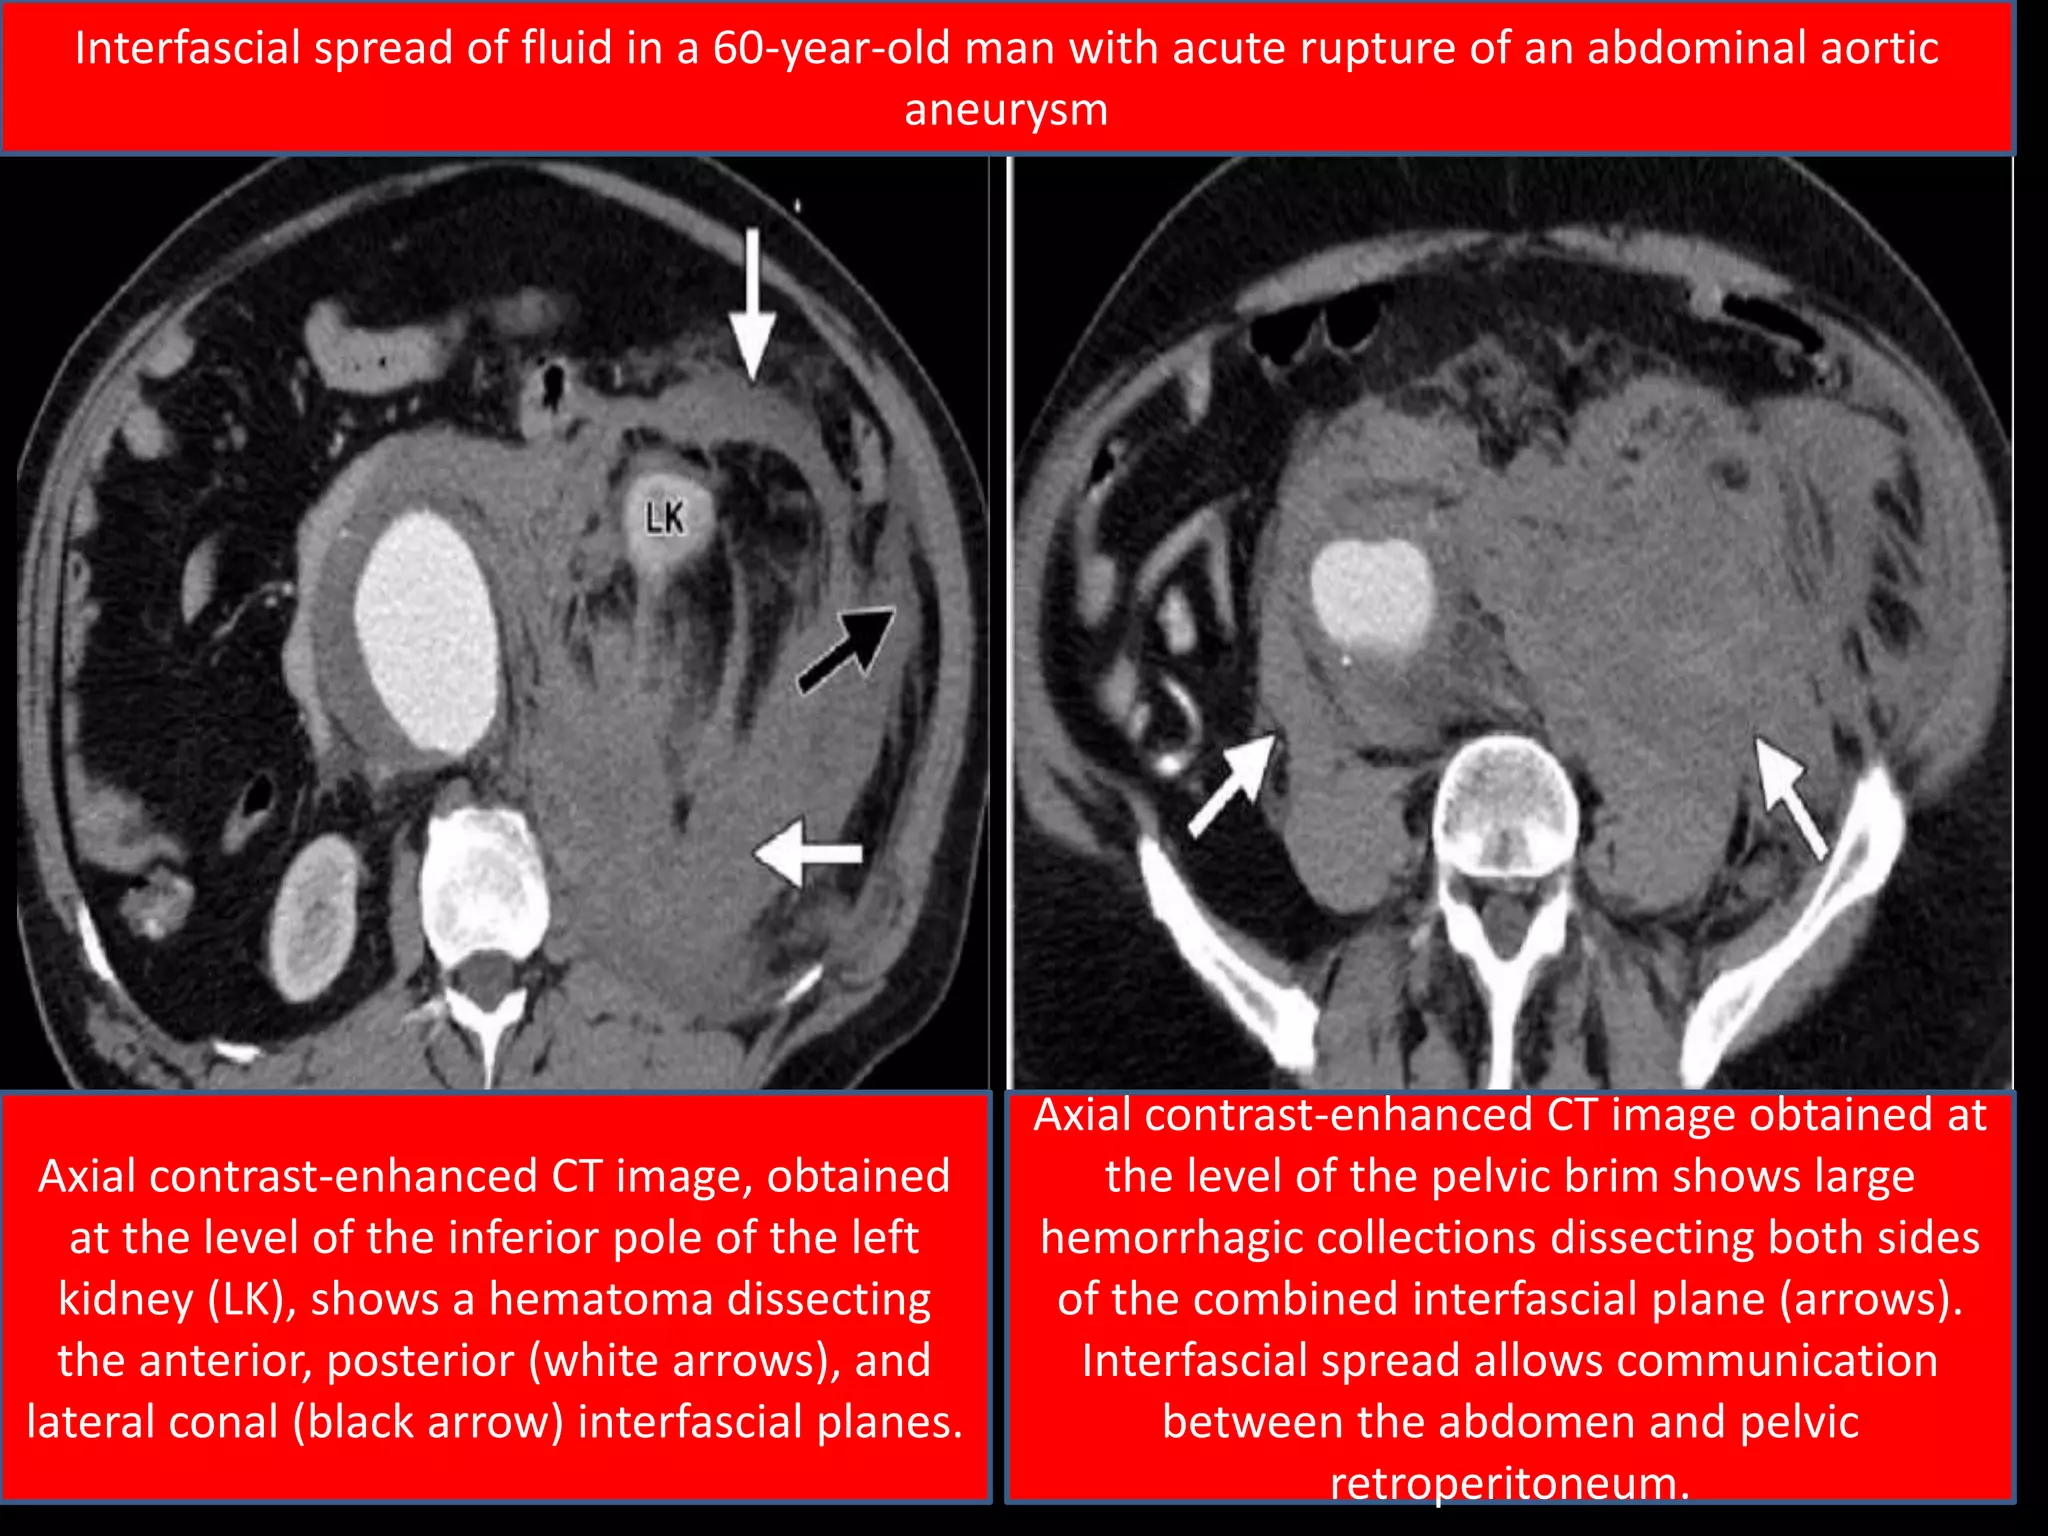

Axial contrast-enhanced CT image, obtained

at the level of the inferior pole of the left

kidney (LK), shows a hematoma dissecting

the anterior, posterior (white arrows), and

lateral conal (black arrow) interfascial planes.

Axial contrast-enhanced CT image obtained at

the level of the pelvic brim shows large

hemorrhagic collections dissecting both sides

of the combined interfascial plane (arrows).

Interfascial spread allows communication

between the abdomen and pelvic

retroperitoneum.

Interfascial spread of fluid in a 60-year-old man with acute rupture of an abdominal aortic

aneurysm